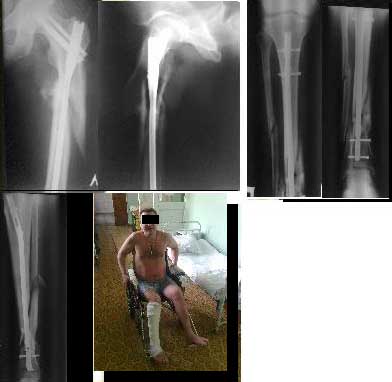

30/09/2011 синтез левого бедра PFN длинный на ортопедическом столе взакрытую.

5.10.2011 синтез правой голени стержнем Деост, в закрытую с применением дистрактора и остеотомией малоберцовой кости. Снимки в приложении. Пациент активизирован, начал передвигаться на коляске, сегодня встал с костылями.

Картинки мелковаты. Голень вроде совсем красиво получилась. Бедро - центральный отломок остался в сгибании. Будем надеяться, это не будет проблемой, и срастется так.